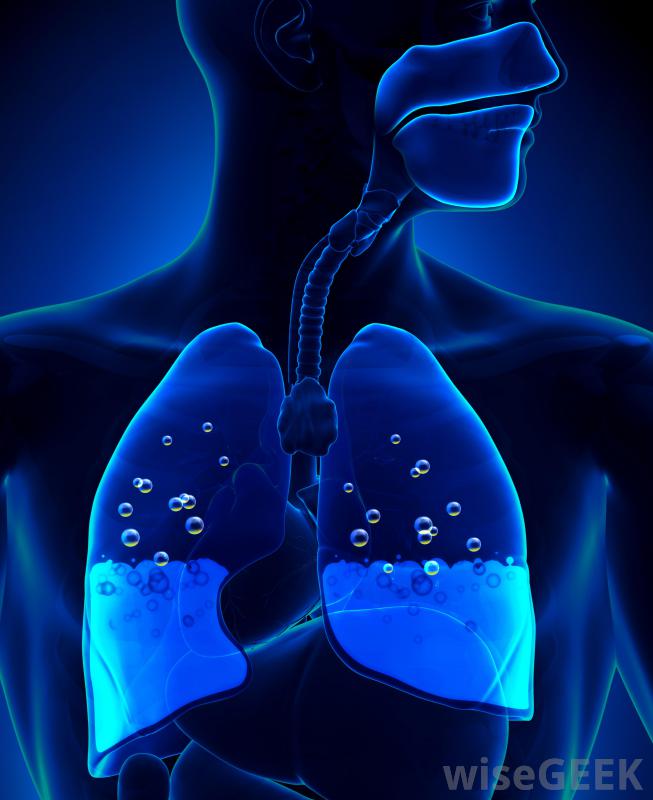

胸腔積液是胸腔內多余液體的積聚,胸腔包圍著肺部。正常情況下,胸膜中含有一層薄薄的液體,以保持肺部在呼吸過程中的平穩運動。當有過多液體時,右側胸腔積液發生在右側胸膜中,右側胸腔積液比左側胸腔積液更容易導致充血性心力衰竭胸腔積液。右側胸腔積液或右側胸腔積液的發生,是一種潛在疾病的結果。右側和左側胸腔的液位通常不同,稱為非對稱性胸腔積液。胸腔積液也可孤立于其中一個空洞,稱為單側胸腔積液。右胸腔積液主要與充血性心力衰竭(CHF)有關胸腔積液是胸腔積液在肺部周圍胸腔中的積聚。胸腔積液的最初癥狀通常是當胸腔中的液體達到一定量時大約500毫升。報告的癥狀包括呼吸困難或疼痛,以及呼吸時胸壁的運動減弱。當胸部和背部被交叉或輕拍時,共振也會減少當用聽診器檢查時,呼吸音可能會很遲鈍,也可能會有不尋常的聲音,如噼啪聲或摩擦聲,這是由于過多的液體產生的摩擦造成的。如果懷疑這些癥狀,通常會進行x光或超聲波檢查以確認診斷右胸腔積液主要與充血性心力衰竭相關。一旦診斷出右胸腔積液或左胸腔積液,則將一根大針放在背部或胸部取出,這一過程被稱為胸腔穿刺術。然后對液體進行分析,以確定液體的成分,以及液體是否滲出或滲出。滲出液表明是全身性的,其中身體的一部分,通常是心臟、肝臟或腎臟,會造成體內液體的整體失衡。滲出液表明肺部或周圍有問題,如細菌或病毒感染、栓塞或癌癥,需要進一步的檢查才能確診。還有其他類型的原因沒有分類,例如自身免疫性疾病和手術引起的積液,但這些并不常見。某些心臟疾病,如右胸腔積液,可以用超聲波檢測出來任何類型的胸腔積液的治療都是基于根本原因,必須治療才能解決整個問題。為了減少胸腔積液,會用針頭將多余的液體抽出。當積液較多時,可以使用引流管或進行手術。其他治療方法包括使用化學藥品治療感染和手術融合胸膜腔以阻止液體積聚。過去,結核是導致胸腔積液的主要原因。任何類型的胸腔積液的治療大多基于潛在原因醫生將傾聽患者的肺部,以診斷右胸腔積液。